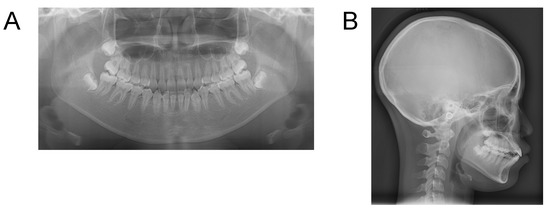

Case 2. Findings from initial examination